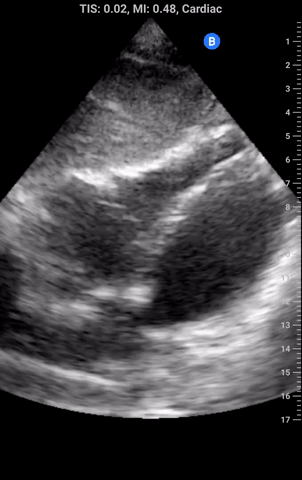

An area that is quite frought with error is the approach, in particular during a cardiac arrest, is to judge whether the RV is dilated as a sign of acute PE. Putting aside the fact that RV frequently becomes dilated during cardiac arrest regardless of the presence of embolus the subcostal view frequently underestimated RV signs as it is generally quite an inferior angle which tends to “shrink” the RV. The views below of the subcostal (left) and A4C (right) are from the same patient which while the RV appears impaired by visual TAPSE in the subcostal views and perhaps moderately enlarged as it is close in size to the LV we see this is a gross underestimate when viewing from the A4C an RV that is dwarfing it neighbour.